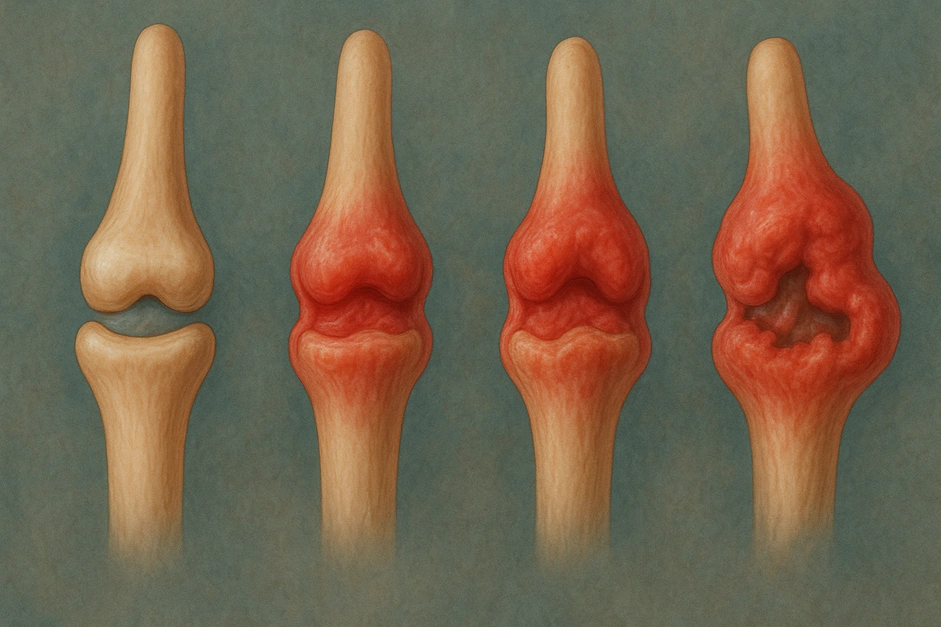

Стадии серонегативного ревматоидного артрита

Состояние развивается поступательно. Каждая стадия отражает глубину воспаления и степень изменения суставных тканей, сроки усредненные:

- Начальная стадия. Воспаление затрагивает синовиальную оболочку. Боль умеренная, скованность появляется после отдыха. Рентген чаще без изменений.

- Развернутая стадия. Появляется отек, ухудшается подвижность, на снимках видна узурация краев суставной поверхности.

- Прогрессирующая стадия. Сустав деформируется, движения ограничиваются, человеку сложнее выполнять бытовые задачи.

- Поздняя стадия. Формируются стойкие изменения. Подвижность резко снижена. Требуется длительная терапия, реабилитация.

При раннем начале базисной терапии прогрессирование можно существенно замедлить, а у части пациентов – остановить развитие эрозий и деформаций.